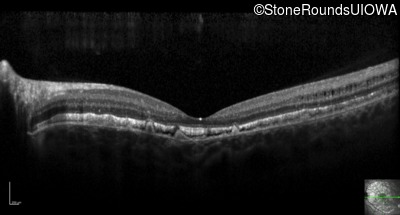

Optical Coherence Tomography - Left - 20/25 -3 sc

Exemplar / OCT Stack